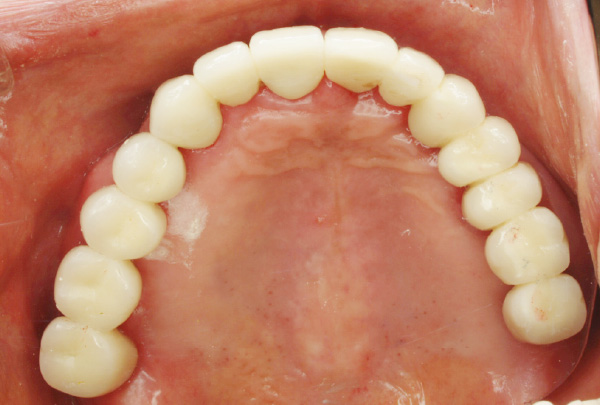

インプラント症例

- AFTER